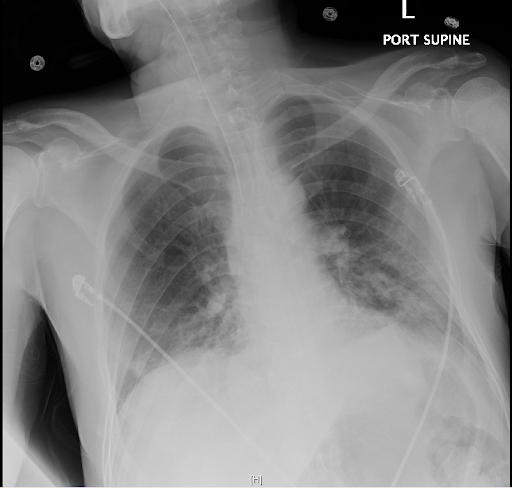

Contributors: Travis Barlock MD, Jeffrey Olson MS4 Feel free to use the cases below for your own practice. All of the scenarios are completely made up and designed to hit several teaching points. Case 1 25 M, presents to the ED with chest pain. Stabbing, started a few hours ago, substernal. Thinks it is GERD. After 2-3 minutes, pain worsens and radiates to the back. VS: BP 125/50 (Right arm 190/110). HR 120. RR of 18. Sat 98% on RA. Additional VS: Temp of 37.2, height of 6'5", BMI of 18. PMH: None, doesn't see a doctor. Meds: None FH: Weird heart thing (Mitral Valve Prolapse), weird lung thing (spontaneous pneumothorax), tall family members with long fingers and toes Physical Exam: Cards: Diastolic decrescendo at the RUSB, diminished S2. UE pulses are asymmetric, LE pulses are asymmetric, carotid pulses are asymmetric, BP is asymmetric MSK: Knees, elbows, and wrists are hypermobile. Imaging: CXR #1 normal, #2 widened mediastinum (no read yet but shows widened mediastinum), POCUS shows small effusion CTA/MRA doesn't come back until after the case. ECG: Sinus Tach Labs: NT-proBNP 500 pg/mL D-Dimer: 7000 ng/L CBC: Hemoglobin: 13.5 g/dL, WBC: 20,000/µL, Platelets: 250,000/µL Chem 7: Na 138, K, 5.7, Cl 102, Bicarb 17, BUN 45, Creatinine: 3.5 mg/dL, Glucose: 180 LFTs: Albumin 2.4, Total protein 5.5, ALP: 140, AST: 3500, ALT: 2800, TBili: 3.2, DirectBili: 2.4, Ca: 7.8 LDH: 2200 PT: 20.5, INR: 2.2, Fibrinogen: 170 5th gen High-Sensitivity Troponin: <3 Lactate: 7 mmol/L VBG: pH 7.22, paCO2 28, bicarb 15 Notes: Can have patient crash somewhere in middle and show 2nd xray Case 2: A 67-year-old female is brought to the ED by her daughter due to progressive weakness, confusion, and fatigue that have worsened over the past week. Unable to get out of bed and has become increasingly lethargic. Also having some nausea, constipation. The daughter denies any preceding illness, recent trauma, or travel. Does not know her meds but will head home to get them after talking with you. VS: BP 88/55 mmHg, HR 110, RR 20, O2 Sat 98% on room air. Additional VS: Temp 36.8°C. PMH: Hypertension, osteoarthritis, and depression. Physical exam: General: Thin, somnolent but arousable. HENT: Dry mucous membranes Neuro: Confused, A&Ox1 (self), hyporeflexia Labs (Includes many that would not return in the ED in case you want to take this case forward to the floor) CBC: WBC 9,500, Hb 16.5, Hct: 50%, Platelets 220,000 Chem7: Na 129, K 2.1, Cl 95, HCO3 34, Creatinine 1.6, BUN 40, Glucose 115 LFTs: normal Magnesium: 1.1 Calcium: 10.8 mg/dL (corrects to 12.8) iCal: 3.2 Phosphate: 2.3 mg/dL Albumin: 2 BUN:Cr ratio: 25 VBG: pH: 7.49, PaCO2 45, HCO3: 34 Lactate: 2.8 Serum Osmolality: 276 mOsm/kg (Osmolal gap of 2) Urine Osmolality: 550 mOsm/kg Urine Sodium (UNa): 10 mEq/L (low). Urine Potassium (UK): 25 mEq/L (elevated). Urine Chloride (UCl): 12 mEq/L (low). Urine Magnesium (UMg): 20 (Elevated). Urine Calcium (UCa): 50 in 24 hrs (Low) 100 cc of urine with foley FeNa Plasma renin activity: 15 mg/mL/hr (elevated), Aldosterone: 25 ng/dL (Elevated), ADH: Elevated, Diuretic screen: Positive for thiazides PTH: 8 (low), HsTrop: 32, Cortisol and ACTH: Normal. EKG: Hypokalemia features CXR: Normal Renal US: shows stones Improves with fluids Note: Can have daughter return with med list at some point including HCTZ, ibuprofen, and sertraline Case 3: Patient Presentation EMS Report: A 27-year-old male involved in a high-speed motorcycle collision is brought to the emergency department by EMS. The patient was found unconscious at the scene with evidence of severe thoracic and extremity trauma. He was intubated en route for airway protection due to altered mental status (GCS 7). VS: HR 130, BP 90/60, RR: bagging at 12 bpm, satting 88% on 100% FiO2 Primary Survey Airway: Endotracheal tube in place. Breathing: Decreased breath sounds on the left side with visible chest asymmetry and paradoxical chest wall movement. Circulation: Mottled extremities noted, with significant deformity of the right thigh. Pulses are diminished in the right leg Disability: GCS remains 7 (E1 V2 M4). Pupils equal and reactive. Exposure: Full-body examination reveals an open fracture of the right femur, multiple abrasions, and bruising over the chest wall. Vent alarms Peak Inspiratory Pressure (PIP) 40 cm H₂O (elevated) Plateau Pressure (Pplat) 35 cm H₂O (elevated) EtCO₂ (End-Tidal CO₂) 55 mmHg High-Pressure Alarm Triggering frequently Glucose 120 CBC: Hgb 8.9, Hct 27, WBC 14.2, platelets 220,000 VBG: pH 7.28, pCO2 33, bicarb 18, lactate 4.5 CXR with tension pneumothorax Patient improves after chest tube, pigtail catheter, or needle decompression. Ready to be transferred upstairs and O2 starts tanking again Vent alarms- second episode Peak Inspiratory Pressure (PIP) 35 cm H₂O (elevated) Plateau Pressure (Pplat) 30 cm H₂O (elevated) EtCO₂ (End-Tidal CO₂) 20 mmHg HR: 140, satting 84%, temp 38.5, ABG: pH 7.32, pCO₂ 30 mmHg, pO₂ 60 mmHg on 100% FiO₂, HCO₃⁻ 18 mmol/L (hypoxemia and metabolic acidosis). D-dimer: Elevated Thrombocytopenia: Platelets 90,000/µL. US shows blown right ventricle ECG shows new RBBB CT PE: Ground glass opacities, consolidation, centrilobular nodules, septal thickening, and fat-attenuating lesions. Note: Management is largely supportive care so once the diagnosis is made, end the case. References Carroll MF, Schade DS. A practical approach to hypercalcemia. Am Fam Physician. 2003 May 1;67(9):1959-66. PMID: 12751658. Coelho SG, Almeida AG. Marfan syndrome revisited: From genetics to the clinic. Rev Port Cardiol (Engl Ed). 2020 Apr;39(4):215-226. English, Portuguese. doi: 10.1016/j.repc.2019.09.008. Epub 2020 May 18. PMID: 32439107. Palmer BF. Metabolic complications associated with use of diuretics. Semin Nephrol. 2011 Nov;31(6):542-52. doi: 10.1016/j.semnephrol.2011.09.009. PMID: 22099511. Reed MJ. Diagnosis and management of acute aortic dissection in the emergency department. Br J Hosp Med (Lond). 2024 Apr 30;85(4):1-9. doi: 10.12968/hmed.2023.0366. PMID: 38708978. Roberts DJ, Leigh-Smith S, Faris PD, Blackmore C, Ball CG, Robertson HL, Dixon E, James MT, Kirkpatrick AW, Kortbeek JB, Stelfox HT. Clinical Presentation of Patients With Tension Pneumothorax: A Systematic Review. Ann Surg. 2015 Jun;261(6):1068-78. doi: 10.1097/SLA.0000000000001073. PMID: 25563887. Rothberg DL, Makarewich CA. Fat Embolism and Fat Embolism Syndrome. J Am Acad Orthop Surg. 2019 Apr 15;27(8):e346-e355. doi: 10.5435/JAAOS-D-17-00571. PMID: 30958807. Produced by Jeffrey Olson, MS4 Special thanks to Evan Fisch MD Get your tickets to Tox Talks Event, Sept 11, 2025: https://emergencymedicalminute.org/events-2/ Donate: https://emergencymedicalminute.org/donate/